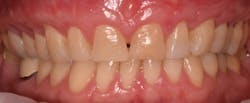

This new biological approach involving blood derivatives A-PRF and I-PRF combined with precision minimally invasive surgery for root coverage demonstrates faster healing without the need of a donor site. The morbidity of GDT is decreased and patient case acceptance is higher compared with traditional grafts. Before-and-after pictures are shown below (figures 15–22).